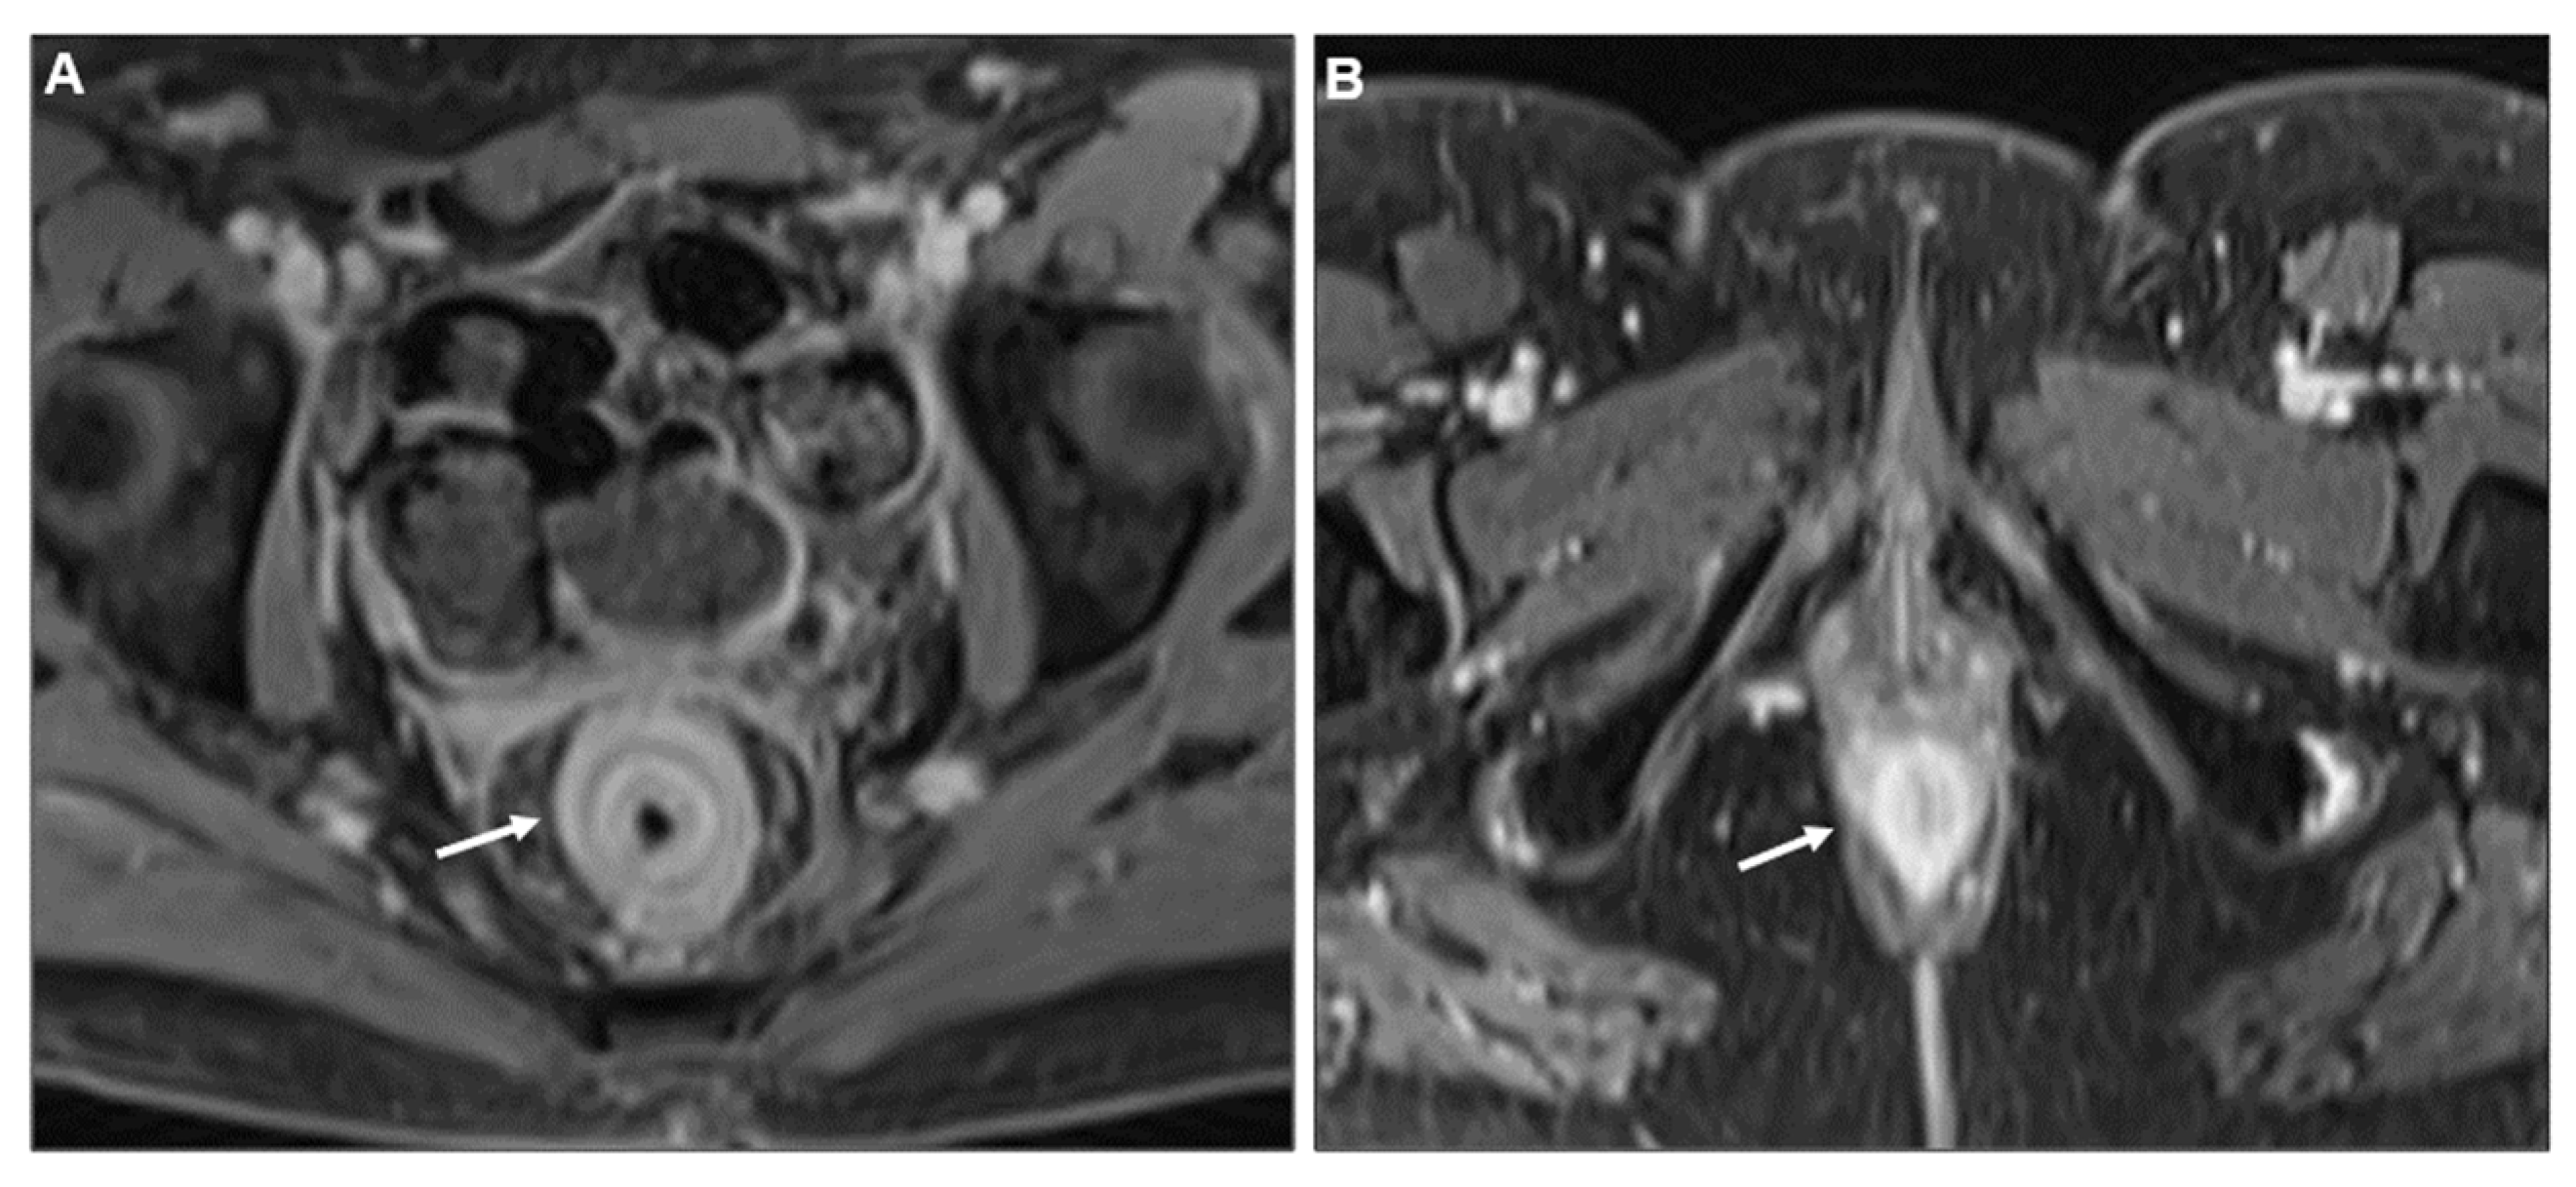

Concentric Ring Pattern